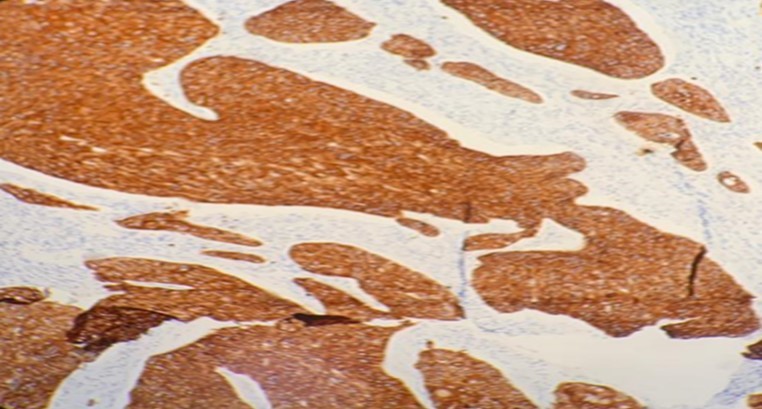

Figure 5.Photomicrograph show positivity to immunohistochemistry marker CK 5/6 in SCC of parotid (x20 high power field)

Photomicrograph show positivity to immunohistochemistry marker CK 5/6 in SCC of parotid   (x20 high power field)

Meanwhile, for primary SCC lesions, the malignant cells show many cytoplasmic processes and desmosomes. Also, the cells have intermediate filaments in their cytoplasm with no secretory granules. These features usually help differentiate primary SCC from the similar-looking MEC. Moreover, SCC malignancies have distinct tumor markers that help pathologists in differentiating it from the rest of the tumors. These tumor markers are p40, CK 5/6 and p63. The use of these markers is as evident in this article.